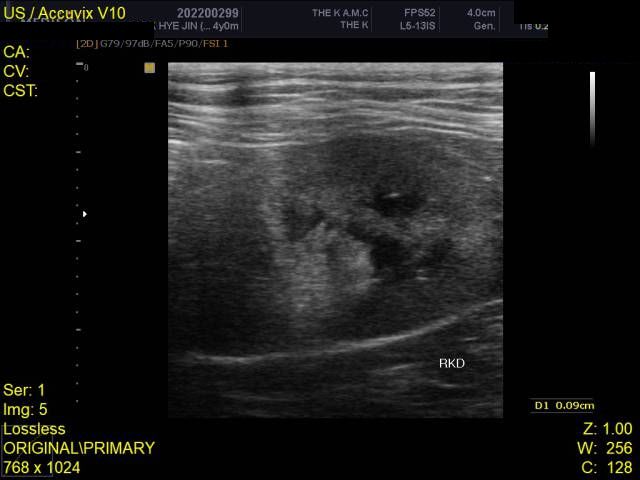

건강검진 때 받은 사진입니다

건강검진 받은 병원에서는 따로 소견을 주지 않으셨으나 지인이 이 사진을 보고

자신의 첫째 고양이가 진단 받았었던 HCM과 엑스레이 사진이 유사하다는 말을 들어서요

HCM의 경우 방사선 상으로는 완전히 진단하는 것이 어렵습니다.

진단을 하려면 영상전문 수의사로부터 심장초음파 소견을 듣는 것이 정확합니다.

HCM이 심할 경우 심장 모양이 valentine shape으로 보이기도 합니다. 아무래도 수의사 선생님이 이런 양상으로 HCM 가능성을 말씀하신 듯하니 심장초음파 진료가 가능한 병원 가셔서 검사 해보시기 바랍니다.

HCM의 진단의 golden standard 는 심장초음파 검사입니다. 하지만 첨부된 자료에는 심장 초음파 검사 결과가 없고

흉부 방사선 검사 또한 외측상이 결여되어 있어 자료로 판단할 수 없습니다.

주치의에게 요청하여 심장 초음파 검사를 진행해 보시기 바랍니다.